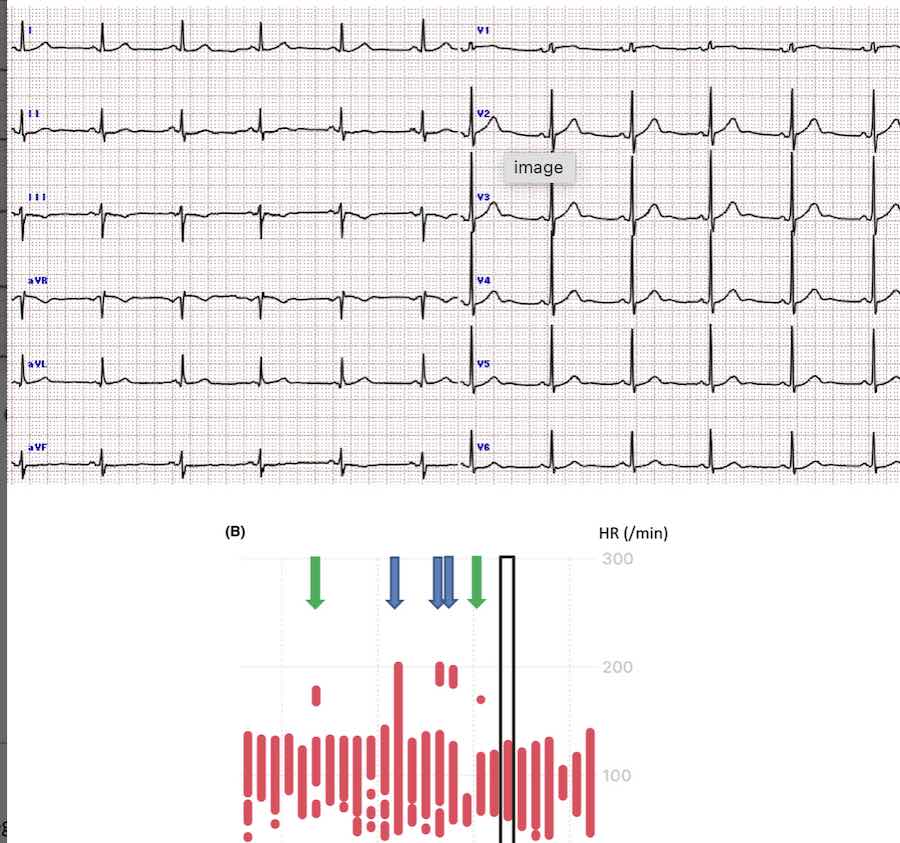

Can Apple Watch Detect Pvc - Apple watch might detect some cases of pvcs secondarily to detecting an irregular. Can apple watch detect ventricular tachycardia? No, apple watch cannot detect pvcs. Also, pvcs interfere with the normal rhythm by coming in before the. The features of the apple watch mention a fib, what about ventricular tachycardia? The ecg app cannot detect a heart attack. To identify a pvc, look for the following characteristics in your ecg: While apple watch doesn’t track pvcs specifically, if you know you’re getting pvcs based on a holter or ecg, you will soon know. If you ever experience chest pain, pressure, tightness, or what you think is a heart attack, call emergency.

To identify a pvc, look for the following characteristics in your ecg: While apple watch doesn’t track pvcs specifically, if you know you’re getting pvcs based on a holter or ecg, you will soon know. Also, pvcs interfere with the normal rhythm by coming in before the. Can apple watch detect ventricular tachycardia? The ecg app cannot detect a heart.

To identify a pvc, look for the following characteristics in your ecg: The features of the apple watch mention a fib, what about ventricular tachycardia? While apple watch doesn’t track pvcs specifically, if you know you’re getting pvcs based on a holter or ecg, you will soon know. The ecg app cannot detect a heart attack. Apple watch might detect.

Can apple watch detect ventricular tachycardia? No, apple watch cannot detect pvcs. To identify a pvc, look for the following characteristics in your ecg: If you ever experience chest pain, pressure, tightness, or what you think is a heart attack, call emergency.